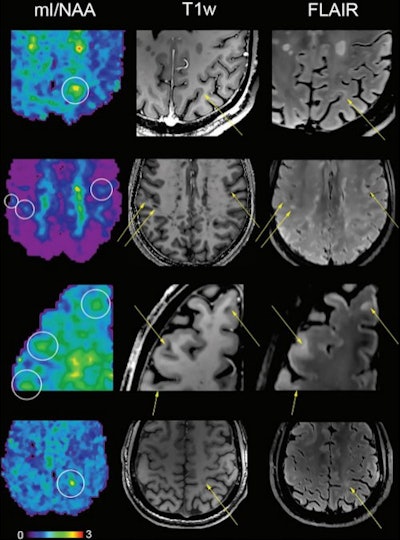

Metabolic maps showing the ratio of myo-inositol to N-acetylaspartate (mI/NAA) clearly depict small subcortical or juxtacortical lesions (circles) that appear inconspicuous at T1-weighted MRI (T1w)/fluid-attenuated inversion-recovery (FLAIR) imaging.

Metabolic maps showing the ratio of myo-inositol to N-acetylaspartate (mI/NAA) clearly depict small subcortical or juxtacortical lesions (circles) that appear inconspicuous at T1-weighted MRI (T1w)/fluid-attenuated inversion-recovery (FLAIR) imaging.The group found the following brain differences in patients with MS: